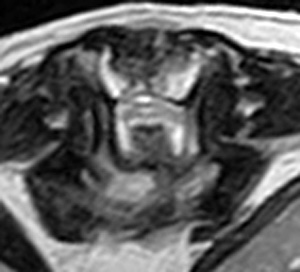

5~6歳以上の去勢手術をしていないオス犬に多い病気ですが、メス犬や去勢した犬に起こることもあります。お尻の筋肉が萎縮した結果、筋肉の隙間から直腸や膀胱が皮膚の下にとびでてしまいます。これにより便が出にくくなったり膀胱炎になったりします。手術をすることで機能回復および今後の致死的な状況を回避することができます。当院では去勢手術→結腸固定→前立腺固定→骨盤隔膜構成筋の縫縮→内閉鎖筋フラップ→浅臀筋フラップの順で通常腹側・臀部左右両側同時に行います。また老化以外に、筋肉が萎縮する原因があったり、腹圧がかかる原因があったりする場合も多いので、再発防止のためそれらの診断・治療も重要です。今回のワンちゃんも無事手術も終わり元気に退院しました。よかったね。